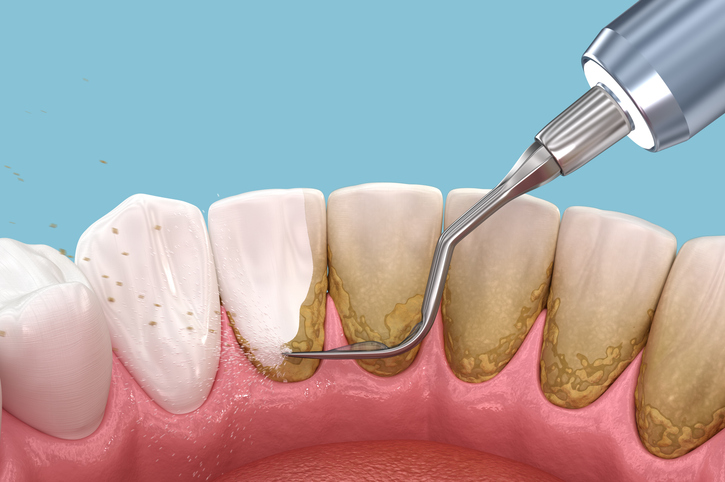

- Scaling and root planing (deep cleaning): Removal of subgingival plaque and tartar, and smoothing of tooth roots. This is a more intensive cleaning procedure, akin to a “deep bath” for your teeth and gums.